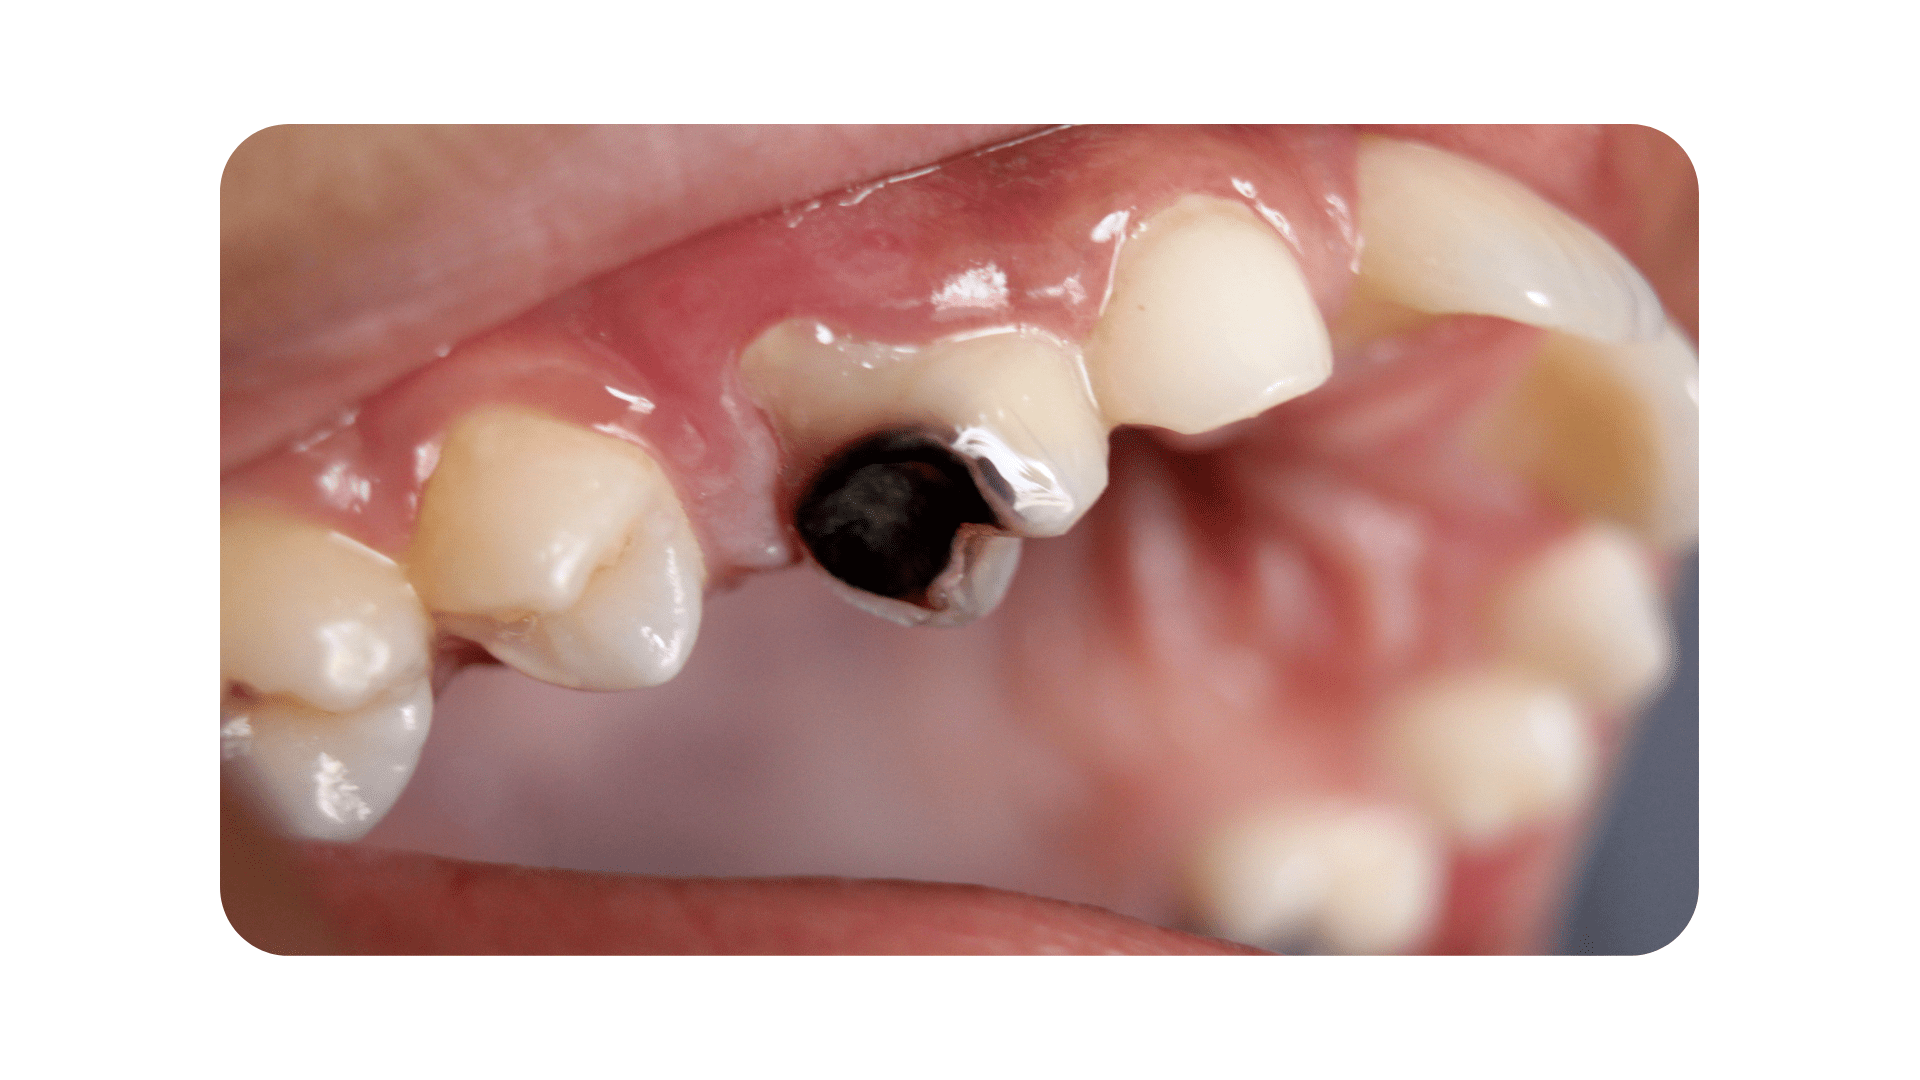

The risk of getting dental decay is not something that should be taken lightly. Cavities can appear unexpectedly, create a severe toothache, and essentially put your life on halt until they are treated. What is tooth decay, and what causes it? The food particles that remain in your mouth after you eat turn into plaque. Acid is produced when the bacteria in plaque break down the sugars and carbohydrates that are present in your mouth. This acid is powerful enough to soften and destroy the enamel, which is the outer coating of a tooth. This condition is known as dental decay, or a cavity. Stages, Symptoms, and Treatments of Tooth Decay

Because tooth decay has numerous stages, there are a variety of symptoms that you may see, feel, or even taste at times. The treatment you will require for your cavity will be determined by how serious the decay is and where it is located. Stage 1: The enamel is decaying. A cavity has not yet passed through the enamel, which is the outer coating of the tooth, during its early stages. During this period, symptoms are not very severe. In fact, you might not notice any of them at all. Sometimes, you may notice that your tooth has darkened, or you may feel a little sensitivity. Our Summerlin dentist will remove the area that has enamel decay and fill the empty space with a tooth-colored filling material in order to repair the decay. Fillings are a quick and inexpensive option that can last for many years. Stage 2: Dentin After the decay has passed through the enamel surface, it will reach the dentin layer. The dentin layer is fragile and is particularly susceptible to decay. This means that if the cavity reaches the dentin, it can spread quickly. During this stage, you will notice that your tooth sensitivity is more pronounced. You might feel uncomfortable when you eat sweets, clean your teeth, or are in chilly conditions. If the decay has impacted much of your tooth, our dentist in Summerlin may suggest that you get a crown instead of a filling. A crown is a hard cap that goes over your tooth and protects it from further harm. Because this treatment is more complex, it does take longer to finish. Additionally, it is more expensive than simply a basic filling. However, if crowns are manufactured and maintained correctly, they can last for many years, making your investment worthwhile. Stage 3: Pulp Chamber The decay will enter the pulp chamber once it has passed through the dentin layer. This is the section of the tooth that has blood arteries, nerves, and connective tissue. Your tooth will become infected after the cavity has reached the pulp. You will go through a lot of discomfort during this time. You may also start to feel uncomfortable due to heat, in addition to chilly weather. You may also experience persistent discomfort that necessitates the use of pain medication to alleviate it. We will take an x-ray of your tooth to make sure that the cavity has reached the pulp chamber. Root canal therapy will be necessary to fix and protect your tooth. This surgery consists of taking out the nerve tissue, cleaning the canals, and closing them off in order to stop bacteria from coming back in. You will probably need to be fitted for a crown in addition to receiving therapy on the nerves of your tooth. This will help to prevent additional harm to the tooth that is already at risk. Stage 4: Abscess The roots of your teeth are the parts that you cannot see when you look inside your mouth. They are located in the jaw. Nerve channels that go down each root extend beyond the pulp chamber. If your cavity has reached the nerves in the root of your tooth, you may have a terrible pain and swelling in your face. If you have an abscess, you will see a little bump on your gums, which is called a fistula. A dental abscess is a major medical issue. You might not find any relief from over-the-counter pain drugs. The toothache could prevent you from sleeping at night or cause you to wake up often. The gum tissue surrounding the tooth that is impacted may swell, and this swelling could migrate to your face. You might possibly develop a fever. If a cavity has caused a serious infection, it may not be possible to salvage the tooth with a root canal. It may be essential to do an extraction. We will be able to determine the state of your tooth and if it can be saved by using a dental x-ray. If it turns out that we need to take it out, a dental implant or a bridge could be a good option for you to replace it. Preventing Cavities Maintaining excellent dental hygiene is the most effective approach to avoid cavities. Make sure to have frequent cleanings and check-ups with your dentist in Las Vegas so that any problems can be addressed as soon as they arise. If you haven't gone to the dentist in a while or think you might have a cavity, you should make an appointment with Dr. Cohan at Summerlin Dental Solutions. Make an appointment by calling or book online today. GET TO KNOW YOUR BEST DENTIST IN SUMMERLIN